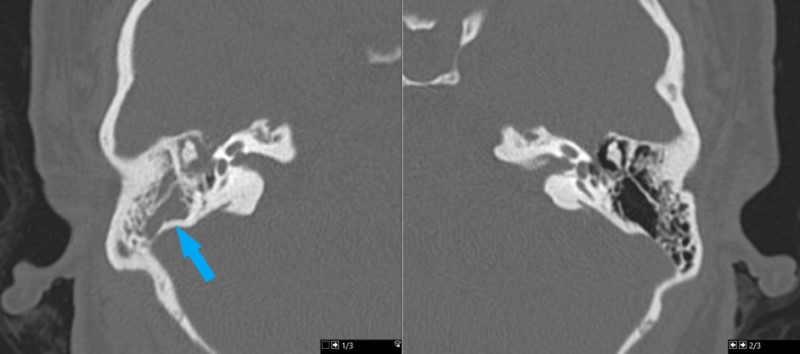

This is a 28 year old female who presents with complaint of right-sided hearing loss and sense of fullness within her right ear.

Her exam is consistent with conductive hearing loss in right ear.